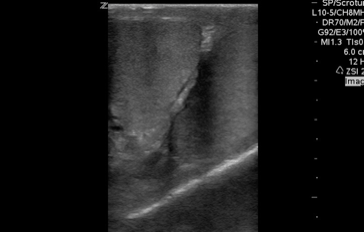

QA of the Day: Great side by side testicular view, looks normal especially that cremasteric reflex! #pocus #foamus